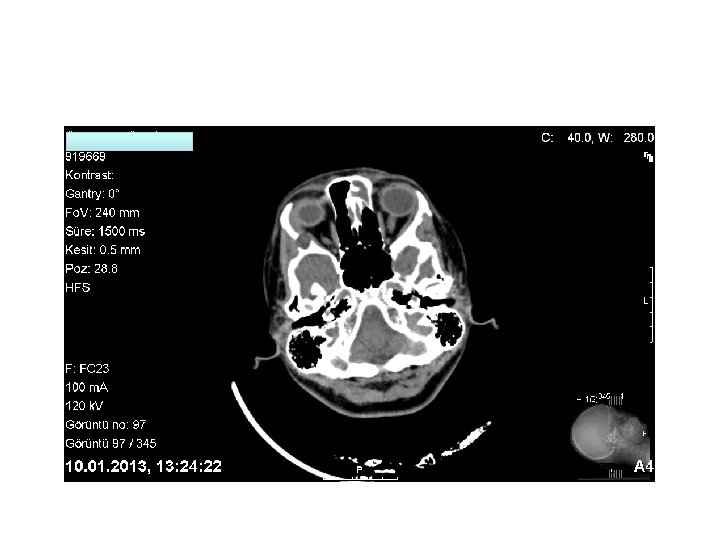

• Sağ orbita lateral duvarda yumuşak doku komponenti olan litik lezyon. Lezyon sol lateral rektus kası ve lakrimal glanda hafif itmektedir.

Kranial MR: • Sağ orbita lateral duvarı komşuluğunda 13 mm çapında kistik natürde kitle lezyonu izlenmektedir. • Sol ethmoid sol frontal sinüste mukozal kalınlaşma izlenmektedir.